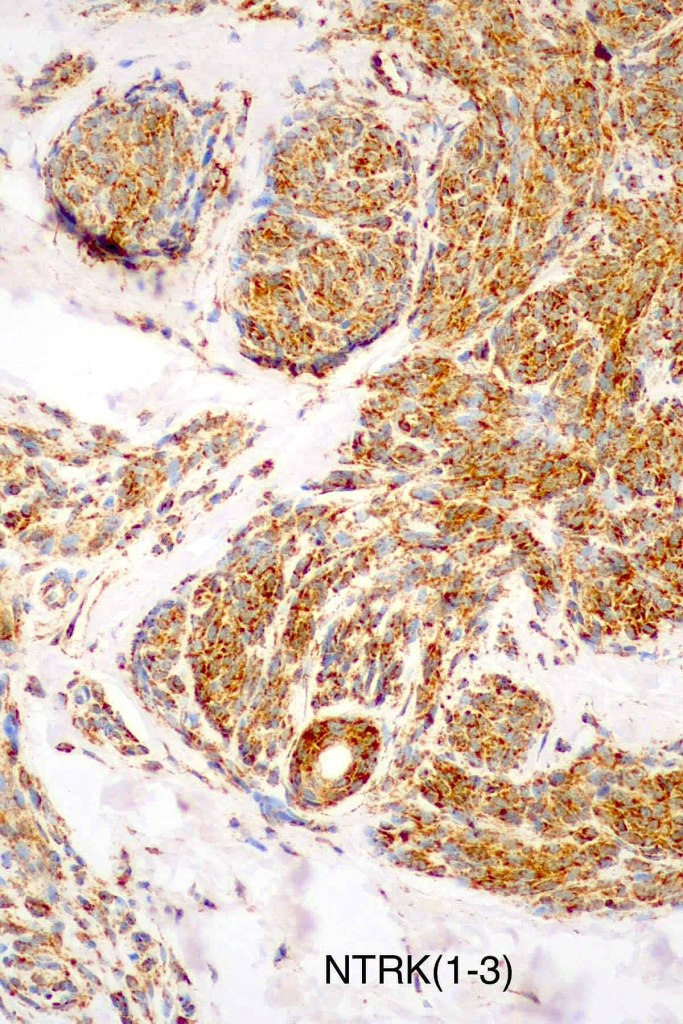

•Spitz nevus has been shown to be associated with receptor tyrosine kinase mutations including ALK, ROS, RET, & NTRK1-3, MET, mutations in HRAS or MAP2Ki, copy number gains of 11p